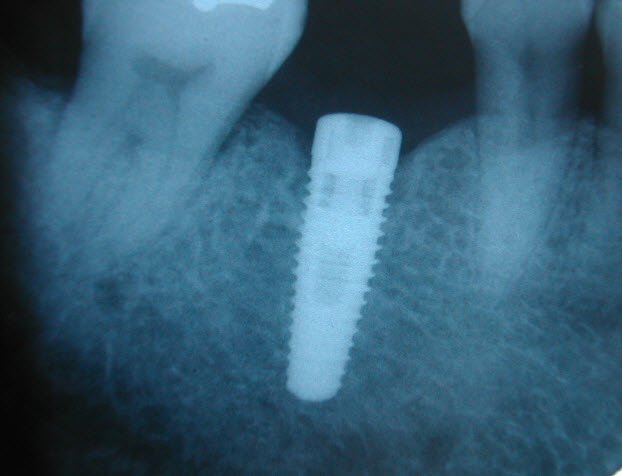

Orangeville Dental Implants

Orangeville Dental Implants                                        Credit Creek Dental offers implant dentistry as an alternative treatment choice.       When ...